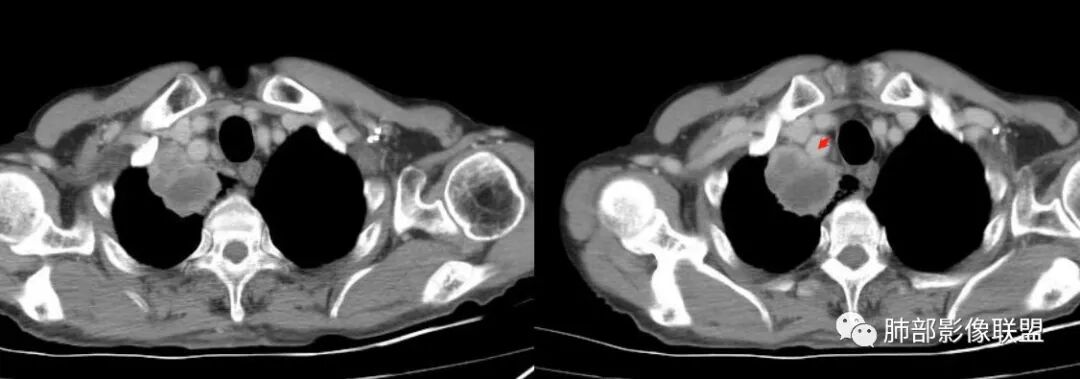

最让人忐忑的:淋巴结

炎性:结核多见,肿瘤:鳞癌多见

最让人放心不下的是这里

南边  :

上腔静脉外面按理没有淋巴结啊

其次:团块影的壁:厚薄不均匀

从上面的图看:炎性肯定有

癌?结核?不能排除

这里想看清楚一下

患者有高血压、脑梗死、肾结石病史,因左胸痛不适入院,伴高热,血常规示白细胞、中性粒细胞高。胸部CT示右肺上叶肿块影,边缘模糊影,内可见低密度坏死,边界清楚,一月后出现气液平面,周围渗出,治疗2周复查液平及周围炎症吸收,肿块未见明显吸收。

考虑肿瘤?右肺上叶高密度影,边缘模糊,侵及纵隔及胸廓入口,病灶密度不均匀,部分支气管截断,增强后不均匀强化,内可见较大范围坏死,纵隔多发肿大淋巴结不均匀强化。肺上沟瘤不能排除。

感染性病变?右肺上叶尖段团块影,中央见大片状状坏死伴液气平面,周围见斑片状高密度影,实验室检查血象明显升高,抗炎治疗后,病灶有所吸收缩小,灶周斑片状消失。